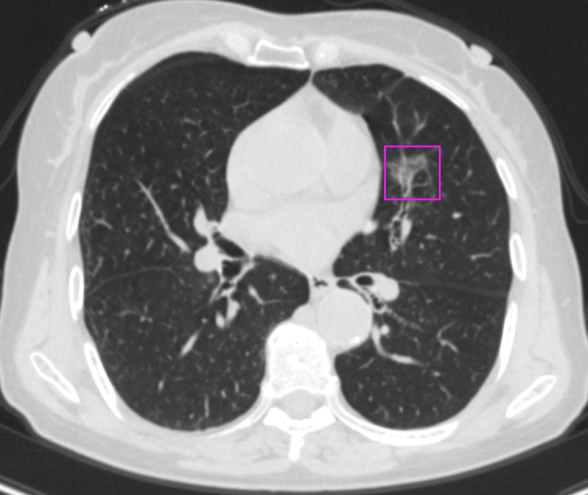

一次感冒,发现双肺结节 患者李女士:“我是由于一次感冒,在老家拍摄胸部CT后发现有双肺结节,后来在家人的陪同下来到市第二人民医院就诊。经过王述波主任团队的手术治疗,顺利地切除了结节,不再担惊受怕了。” 在发现肺结节1个月后,李女士被王述波主任手术团队接诊。团队进行评估发现,该患者CT提示右肺上叶毛刺状结节、左肺上叶混合密度结节,考虑早期肺肿瘤可能性大。(右肺上叶前段结节;左肺上叶上舌段结节) “量体裁衣“精准手术,术后4天康复出院 王述波、王永明主任团队在胸外手术规划系统的指导下,经过术前评估和讨论,决定采取分阶段的手术方案以最大程度地确保手术的成功和患者的安全。 首先,对患者右肺上叶前段采用肺段切除手术进行优先处理。利用系统提供的精准定位功能,准确识别结节周围的血管位置、安全切除范围。术中,在胸腔镜下准确裁剪,保证切缘,确认切除了患者右肺上叶前段肺组织。 最终这例手术过程顺利,术后患者4天康复出院,没有不良反应。(右肺上叶前段病灶阻断血管三维重建图) AI+3D助力手术,消除患者后顾之忧 潍坊市第二人民医院(潍坊呼吸病医院)2024年初引进的3D手术规划系统,为每位患者量身定制了精准的手术方案,在AI+三维重建技术的加持下,为实现精准的肺段及肺亚段切除提供了强有力的支持,达到“量体裁衣”的目的。在术前患者能够清晰了解治疗过程,解除了早期肺癌可能带来的焦虑感,使得治疗过程更加透明和可信。 健康之路,我们与您同行 潍坊市第二人民医院(潍坊呼吸病医院)胸外科是市级医学重点学科,全科医护人员以学科建设、新技术引进和创新为切入点,加强人才培养和引进,现已形成集医疗、教学、科研于一体,具有明显特色和优势的学科。近年来,胸外科开展了气管支气管成形术,肺、食管联合切除手术、单孔胸腔镜肺叶切除、单孔胸腔镜肺段切除、胸腔镜下袖式切除、人工胸骨移植手术、食管癌二切口、三切口,二、三野淋巴清扫等一系列高难度手术,居国内领先水平。由胸外科领衔的肿瘤综合治疗会诊制度,涉及到胸外、呼吸、肿瘤内科、放疗科、放射科等多个专业,对每一位胸部肿瘤患者就诊断、鉴别诊断、治疗及预后等方面进行多学科会诊,受到了全市乃至全省专业同行的认可。咨询电话:0536—8214091/8214109 科普链接 胸腔镜下肺段切除术胸腔镜下肺段切除术,又称胸腔镜下解剖性肺段切除术,采用微创方式将小病变所在的肺段精准切除,在保证肿瘤手术根治的同时,最大限度保留了正常的肺组织,降低了肺功能的损失,实现了真正意义上的微创。